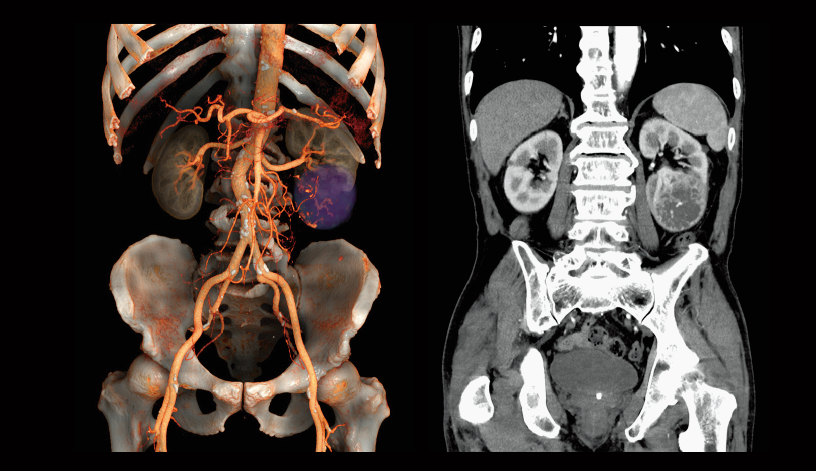

Intraoperative oxygen desaturation (Left)

Left common iliac artery occlusion (Right)